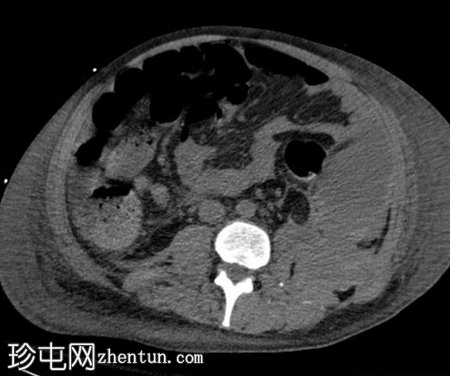

CT

腹部和盆腔非造影CT扫描显示腹水和大面积浅表软组织水肿。

左下腹局部积液,密度略有增高,呈层状分布,提示可能存在腹腔积血。

左髋前部肌肉组织存在额外异常密度影,疑似血肿。无潜在急性骨性异常。